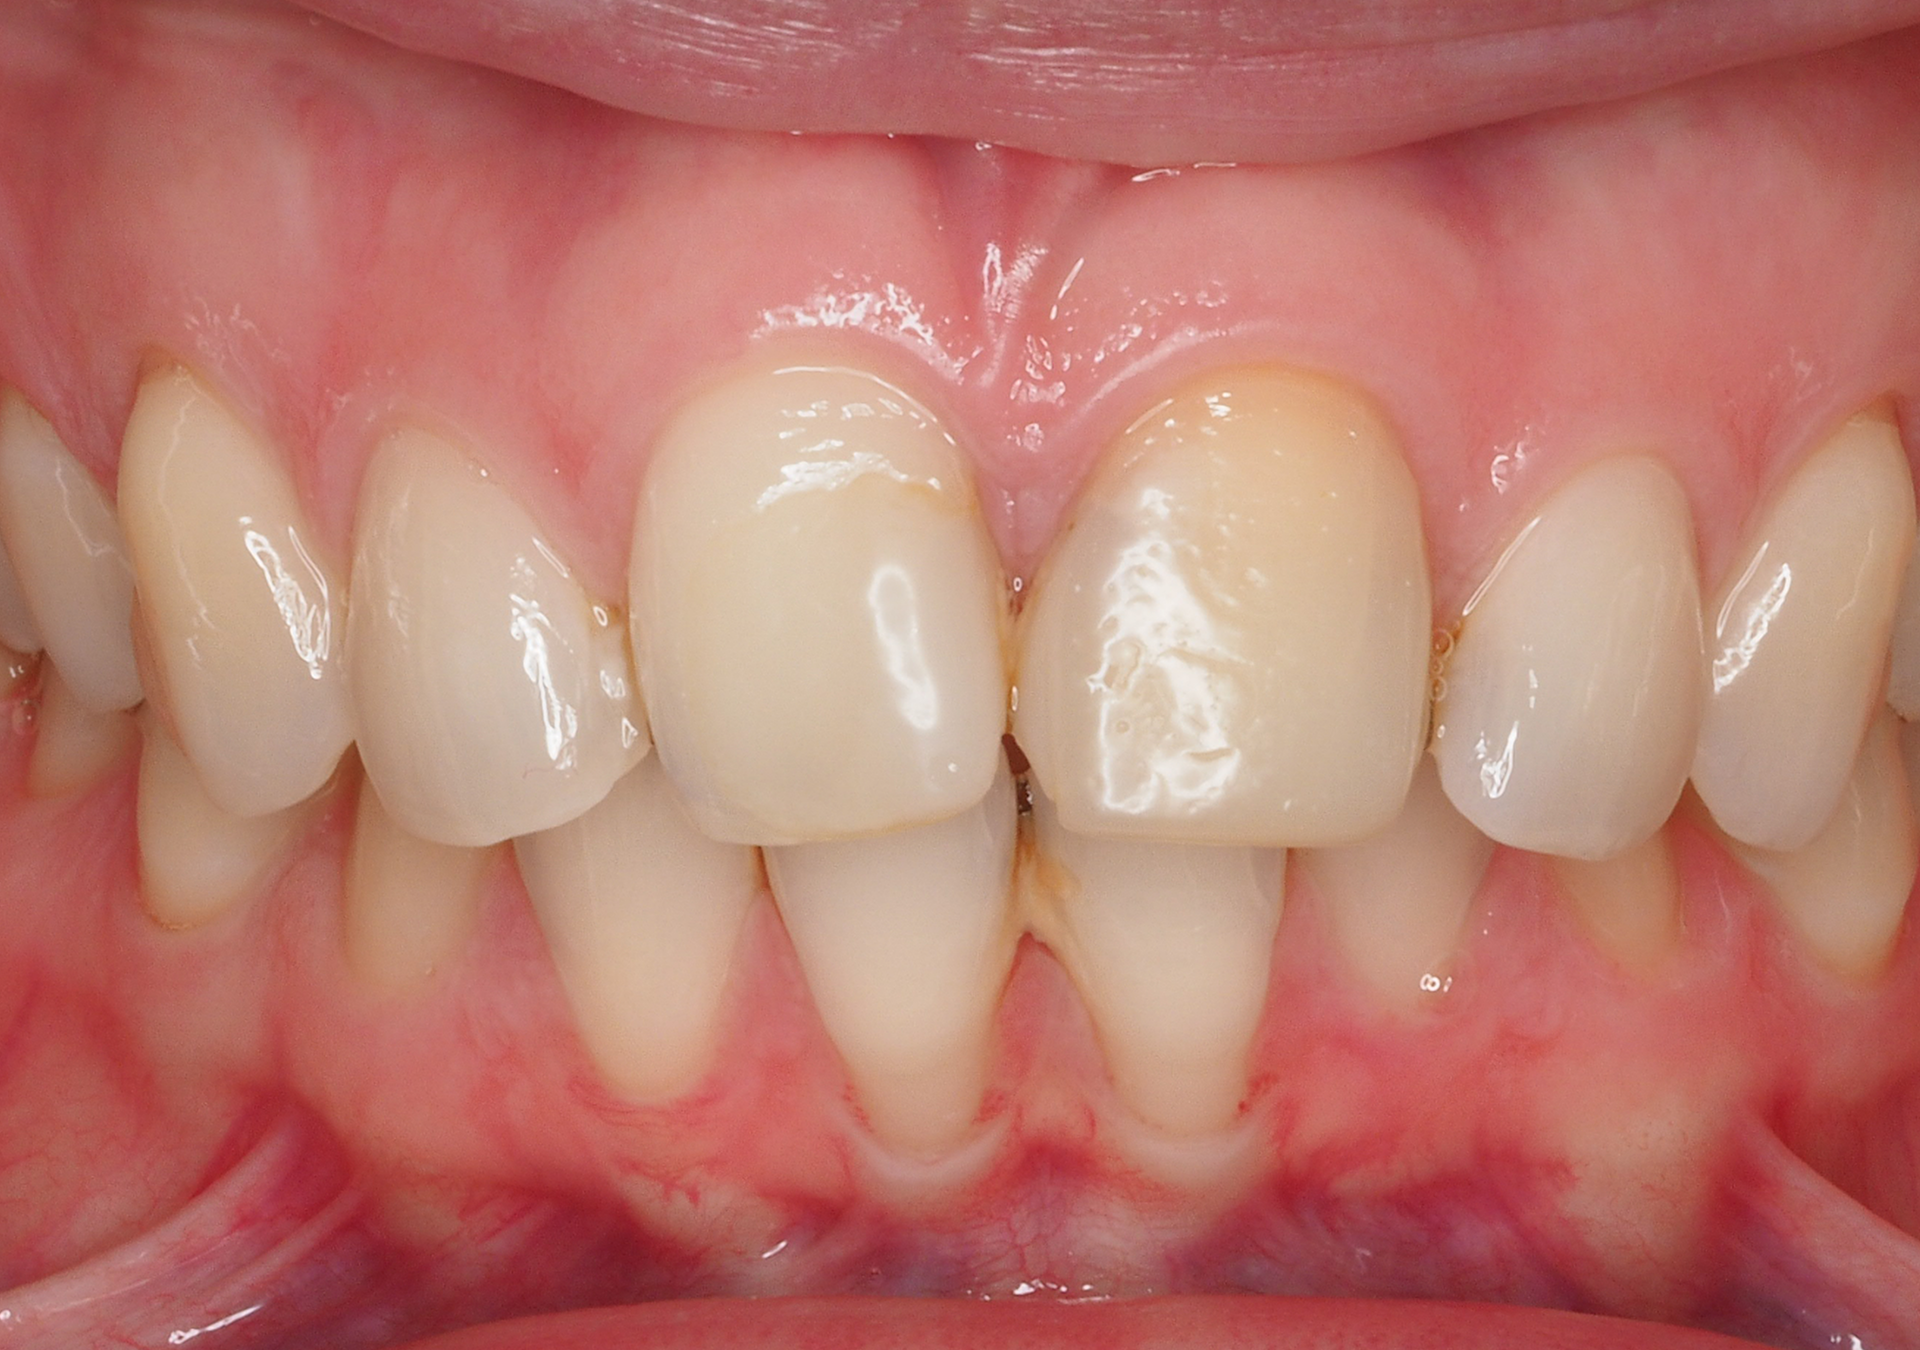

Restauración cerámica

- Experiencia en la rehabilitación de casos complejos.

- Diseño de sonrisa y prueba estética previos para visualizar los resultados antes de iniciar el tratamiento.

- Coordinación con laboratorios de máximo nivel para lograr resultados estéticos y funcionales excelentes.